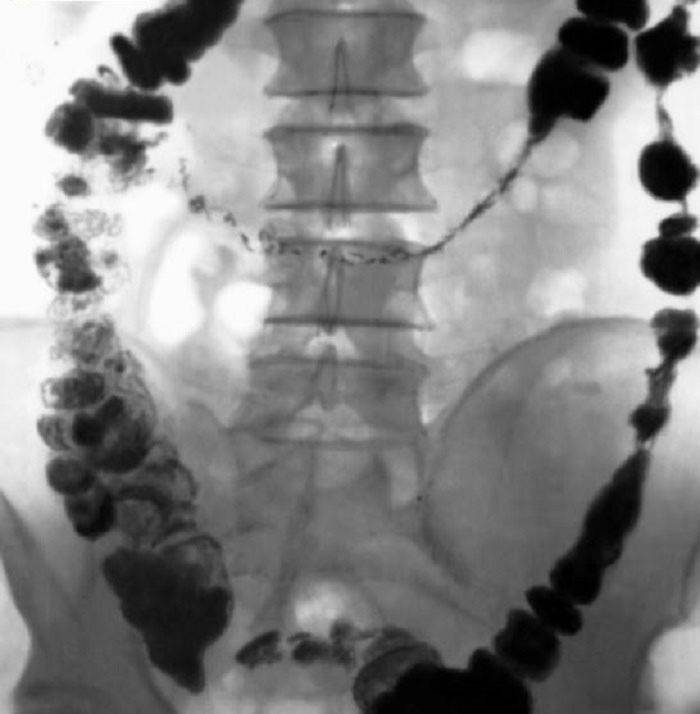

diagnostika

Ak existuje podozrenie na narušenie črevnej motility a prítomnosť atónie vrátane, je nevyhnutné poradiť sa s proktorom alebo gastroenterológom s cieľom stanoviť presnú diagnózu, určiť závažnosť choroby a príčinu jej výskytu. Pretože samoliečba môže viesť k zhoršeniu a atónii!

Lekári ľahko diagnostikujú atómiu na základe výsledkov prieskumu pacienta o príznakoch choroby, ktorá sa ho týka. Je oveľa ťažšie zistiť príčinu choroby. Na tento účel sa používajú tieto metódy liečby atónie:

-

Prieskum zameraný na určenie životného štýlu pacienta, jeho stravovacích návykov a dedičnej predispozície k atónii;

- Analýza stolice a stolice;

- kolonoskopia;

- Röntgen (v niektorých prípadoch röntgenové snímky ukazujú miesta akumulácie výkalov, čo pomáha identifikovať miesta možných adhézií alebo fekálnych krvných zrazenín v čreve).